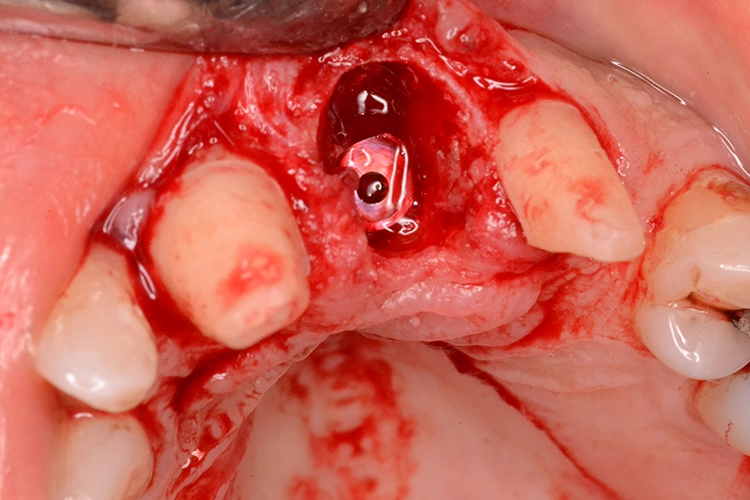

5. Multiple Sofortimplantationen in Zusammenhang mit internem Sinuslift

Beim vorliegenden 54-jährigen Patienten mussten aufgrund von lokaler Parodontitis die Zähne 25, 26 und 27 entfernt werden. Im apikalen Bereich lag jedoch gesunder Kieferknochen vor, sodass eine Sofortimplantation möglich war. Aufgrund der guten Einsichtbarkeit des Operationsgebietes nach Zahnextraktion konnte in diesem Fall flapless vorgegangen werden.

Dr. Plöger

In regio 26 konnte das Implantat dabei komplett apikal im gesunden Knochen verankert werden. In regio 27 jedoch wurde lediglich eine Restknochenhöhe von 8 mm bestimmt. In diesem Fall wurde die Sofortimplantation mit einer internen Sinusbodenelevation nach Summerset kombiniert.

Da zur Aufweitung der Trifurkation die Densah Versah Burs im Rückwärtslauf eingesetzt wurden, kann durch die Osseodensifikation auch der Kieferhöhlenboden bis zu einem bestimmten Umfang mit dieser Technik der Knochenverdrängung angehoben werden. Wird die Kieferhöhle tatsächlich eröffnet, kann auch Knochenersatzmaterial durch den Bohrstollen in die Kieferhöhle augmentiert werden, unter der Voraussetzung einer intakten Kieferhöhlenmembran.

Aufgrund der Rückwärtsdrehung der Bohrer ist die Perforationswahrscheinlichkeit der Membran jedoch nicht höher als bei konventionellen Verfahren. Sollte die Membran tatsächlich perforiert werden, muss gegebenenfalls auch eine externe Sinusoperation mit Verschluss des Membrandefektes angeschlossen werden.